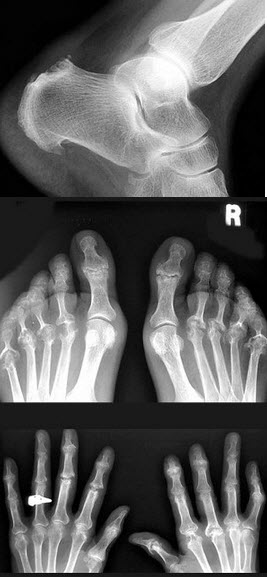

221、单项选择题

女,52岁,足跟痛,手指运动僵硬,结合图像,最可能的诊断是()

A.骨质疏松症

B.骨脓肿

C.骨囊肿

D.骨折

E.类风湿关节炎